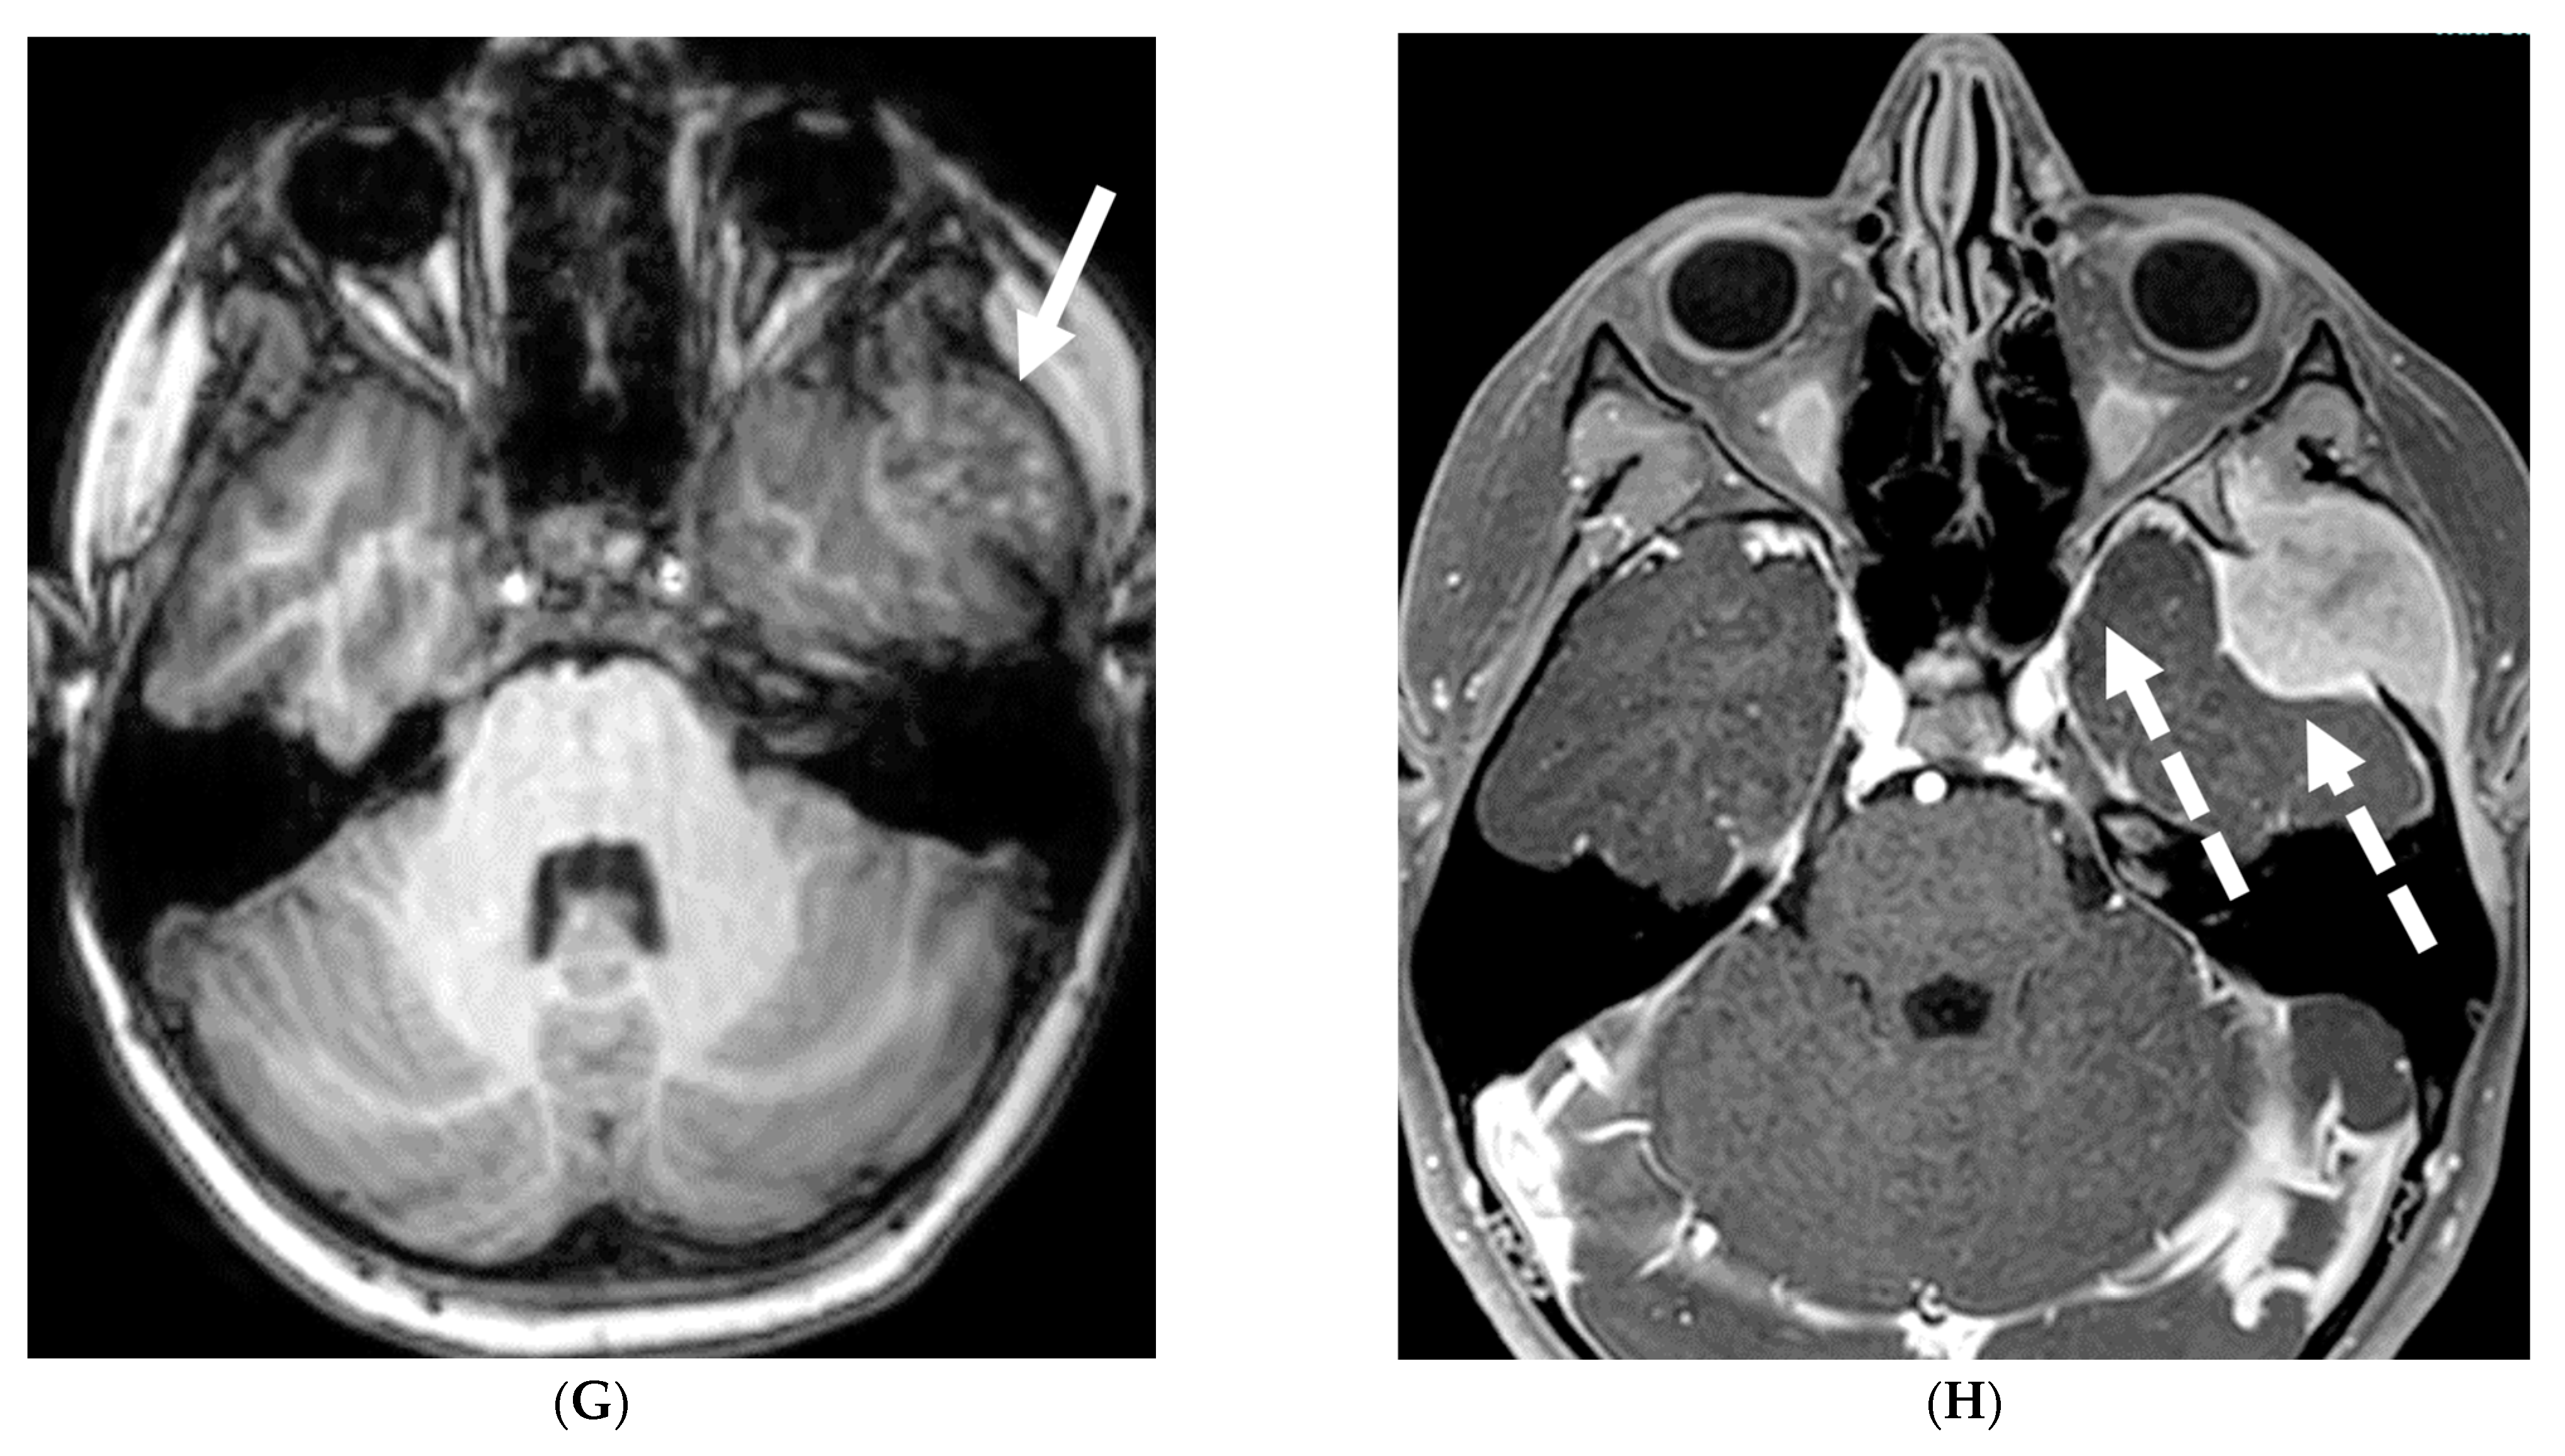

5.2. Fungal Meningitis

Fungal infections of the central nervous system (CNS) can be broadly categorized into two forms based on the causative organism’s size and pathogenesis. Yeast infections (e.g., Cryptococcus, Candida) are smaller and disseminate hematogenously, resulting in parenchymal granulomas, abscesses, and diffuse leptomeningitis. Mold infections (e.g., Aspergillus, Mucorales) are larger fungi that are restricted from entering the meningeal microcirculation, leading to more focal disease manifestations such as cerebritis, abscess formation, vasculitis, infarct, and mycotic aneurysm [99]. Candida is the most common fungal organism affecting children, typically in preterm and/or low birth weight neonates [100]. The routes of CNS invasion by fungal pathogens include hematogenous dissemination from a distant source (commonly lung), direct inoculation following trauma or neurosurgical procedures, and local extension from adjacent structures like the paranasal sinuses, orbit, or spine [101].

MRI findings in fungal meningitis include LME, which can be smooth or thick, nodular and irregular, and commonly involve the cortical sulci [102]. While a smooth, linear enhancement pattern is common in viral and bacterial meningitis, it can also be seen in immunocompetent patients with fungal meningitis [102]. Inflammatory exudates containing cell debris, fibrin, and hemorrhage can deposit in the subarachnoid space, leading to arachnoiditis. Protein accumulation in the subarachnoid space shortens T1 relaxation time and results in increased signal intensity on FLAIR sequences [102]. Meningeal adhesions can obstruct arachnoid granulations, leading to impaired cerebrospinal fluid (CSF) drainage and secondary hydrocephalus. Fungal brain abscesses typically demonstrate a central T1 hypointense and T2 hyperintense core, surrounded by a T1 iso-to-hyperintense and T2 hypointense enhancing peripheral rim (Figure 20) [103,104].

Figure 20.

Axial T2 (A), axial DWI (B), axial SWI (C) and axial T1 post contrast (D): 4-year-old girl with acute lymphoblastic leukemia, pancytopenia and fever. Treatment started one week before with asparaginase. There is prominently T2 hyperintensity and swelling of the gyri involving the medial aspect of the left parietal occipital cortex (arrow). Multiple small foci of T2 hypointensities are identified within the involved region with corresponding blooming on the susceptibility indicating hemorrhage (curved arrow) and peripheral rim of true restricted diffusion (dashed arrow). Postcontrast images show pachymeningeal and LME in the involved region (open arrows). Features are concerning for fungal infection. Pathology revealed Rhizomucor pusillis (thermophilic fungus).

5.4. Granulomatosis Polyarteritis (GPA)

GPA is an autoimmune necrotizing granulomatous inflammation associated with anti-neutrophil cytoplasmic antibody (ANCA) vasculitis. This multisystem disorder predominantly affects small vessels, causing endothelial injury and tissue damage in the upper and lower respiratory tract and renal system [109,110]. Neurologic involvement occurs in 20–50% of GPA patients, mediated by three main mechanisms: vasculitis of cerebral vessels, granuloma formation due to contiguous involvement from adjacent paranasal and orbital lesions, and remote granulomatous lesions in brain parenchyma or meninges [111,112]. Patients typically present with headache, altered mental status, and transient ischemic attacks. Pituitary gland involvement can manifest as hyperprolactinemia or diabetes insipidus [111].

Imaging findings in GPA include chronic hypertrophic pachymeningitis (most common) representing granulomatous involvement. This can be diffuse or focal, with the latter showing dural thickening and enhancement adjacent to a sinus or orbit [113]. Tentorium involvement is common, presenting as the ‘Eiffel by night’ sign [114]. Cerebral vasculitis appears as multiple T2 hyperintense white matter lesions potentially showing diffusion restriction and patchy enhancement. Cerebral atrophy may be observed, attributed to steroid treatment and/or vasculitis. Pituitary involvement can range from normal to enlarged gland size, with thickened stalk and peripheral enhancement. Cranial nerve involvement, particularly of the olfactory and optic nerves, is common due to mass effect from adjacent lesions or hypertrophic pachymeningitis (Figure 22) [112].

Figure 22.

Post contrast axial FLAIR (A), axial T1 FS (B), sagittal T1 Right (C) and Left (D): 10-year-old girl with elevated ANCA, headache and mild LUE weakness. There is bilateral anterior temporal smooth dural enhancement (white arrows). Diagnosis: Antineutrophilic cytoplasmic antibody (ANCA) associated vasculitis, likely granulomatosis with polyangiitis.